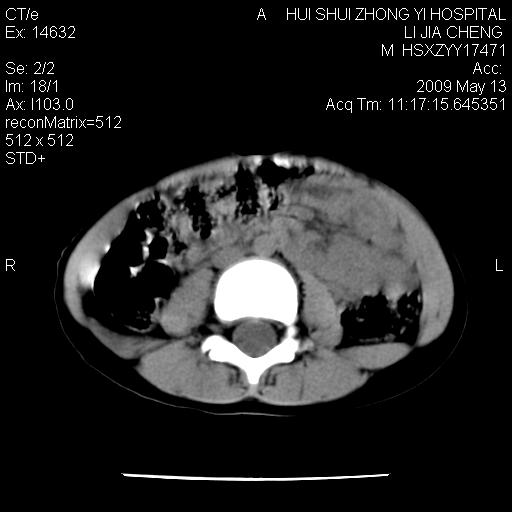

脂肪肉瘤可能性大,大血管边界不清,特别是腔静脉。不除外其他腹膜后肿瘤。

来源于十二指肠水平部病变?建议行进一步检查。

考虑腹疝可能。